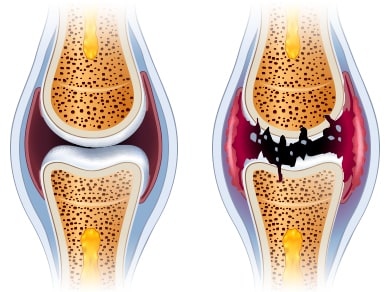

관절염의 원인은 단일하지 않으며, 병원체 감염, 유전적 취약성, 환경적 요인 등이 복합적으로 작용합니다. 원인을 알 수 없는 자가면역성 염증이 관절을 공격하면서 양쪽성 활막염을 일으키고, 장기적으로는 관절 파괴와 기능 저하를 초래할 수 있습니다.

대부분 환자는 시간 경과에 따라 증상이 완화와 악화를 반복하며, 적절히 관리하지 않으면 관절 구조와 주변 조직이 손상되어 관절 기능 상실로 이어질 수 있습니다. 활동적인 시기인 30대 전후에도 발병할 수 있고, 고령층(60세 이상)에서도 흔히 나타납니다. 스트레스가 많은 사람이나 체중이 높은 경우 위험이 커질 수 있으며, 여성의 발병률이 남성보다 높습니다.